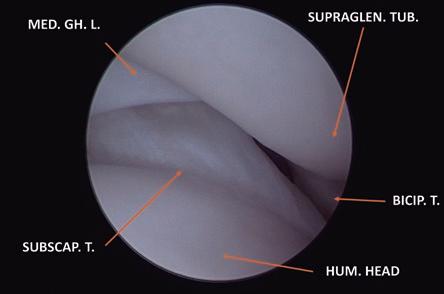

Se presenta el caso de una gata sometida a craneotomía supratemporal para exéresis de un menigioma, en la que se realizó un mantenimiento anestésico intravenoso para mantener una mayor estabilidad hemodinámica durante la cirugía.

Maine Coon, hembra castrada de 8 años, 3,5 kg y condición corporal 5/9, diagnosticada mediante resonancia magnética de una lesión extradural que afectaba a los lóbulos parietal, temporal y occipital (posiblemente meningioma) y que le producía un cuadro de circling, que en el momento de la anestesia estaba controlado gracias al tratamiento con dexametasona 0,15 mg/ kg/24 h. Como otros antecedentes clínicos, la paciente presentaba barro biliar, iniciándose el tratamiento con ácido ursodesoxicólico.